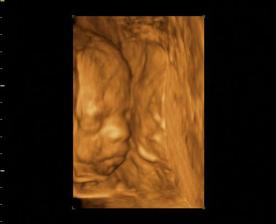

22.augusta 2008 sa náš drobček narodí cisárskym rezom nevieme sa toho dňa dočkať.